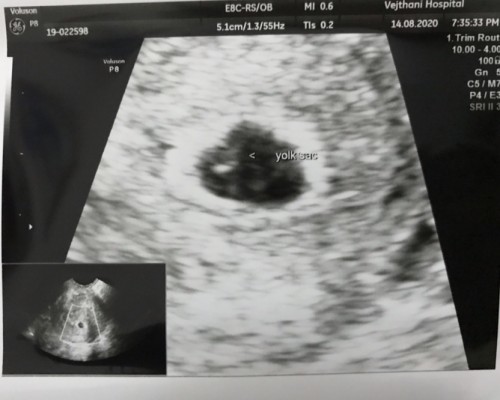

ตอนนี้อายุครรภ์แค่5สัปดาห์นิดๆค่ะ เมื่อวานมีเลือดสีชมพูซึมๆออกเล็กน้อย หลังปัสสาวะแล้วใช้ทิชชู่ซับดูแล้วเจอค่ะ รีบไปหาคุณหมออัลตราซาวด์ดูครั้งแรก เจอถุงตั้งครรภ์ เจอไข่แดง อยู่ในตำแหน่งดี อยากทราบว่าอันตรายไหมคะ แม่ๆท่านไหนเคยมีประสบการณ์เลือดออกขณะตั้งครรภ์ไตรมาสแรกไหมคะมาแชร์กันหน่อยค่า กลัวว่าจะแท้งมากๆเลย 😭#ขอบคุณล่วงหน้านะคะ